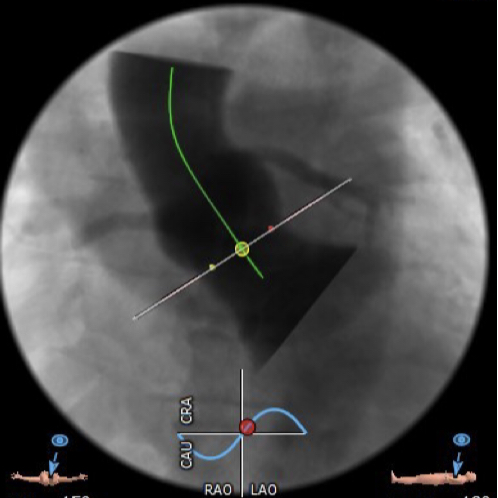

在放射科,超声科和麻醉科的通力协作下,顺利完成了术前准备,术者团队在术中谨慎建立轨道,根据主动脉根部造影的结果,初步判断释放体位是否合适观察瓣叶活动度、是否合并反流,选择合适的跨瓣体位。瓣膜释放前优先确认猪尾管位置,避免瓣膜在释放过程中脱载。